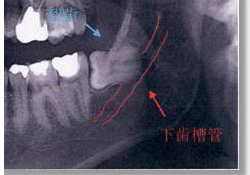

下顎の骨の中には、下歯槽管というトンネルがあり、下顎の後ろの方から下唇の斜め下ぐらいまで続いています。この中には神経と血管が走行しており、この神経(下歯槽神経といいます)は、骨の中のトンネルを出た後、下唇周囲まで枝を伸ばし、主に歯の感覚や、下唇とその周囲の感覚を担当しています。抜歯の際に問題になるのは、智歯の根の先と下歯槽管の位置関係です。根の先がトンネル内に突出していた場合、抜歯によりトンネル内に穴があき、神経血管の損傷の原因になります。血管損傷時には、強い出血により抜歯を中止する事もあり得ます。

智歯の根の先は下歯槽管内に突出し、抜歯による神経損傷の可能性が高い。